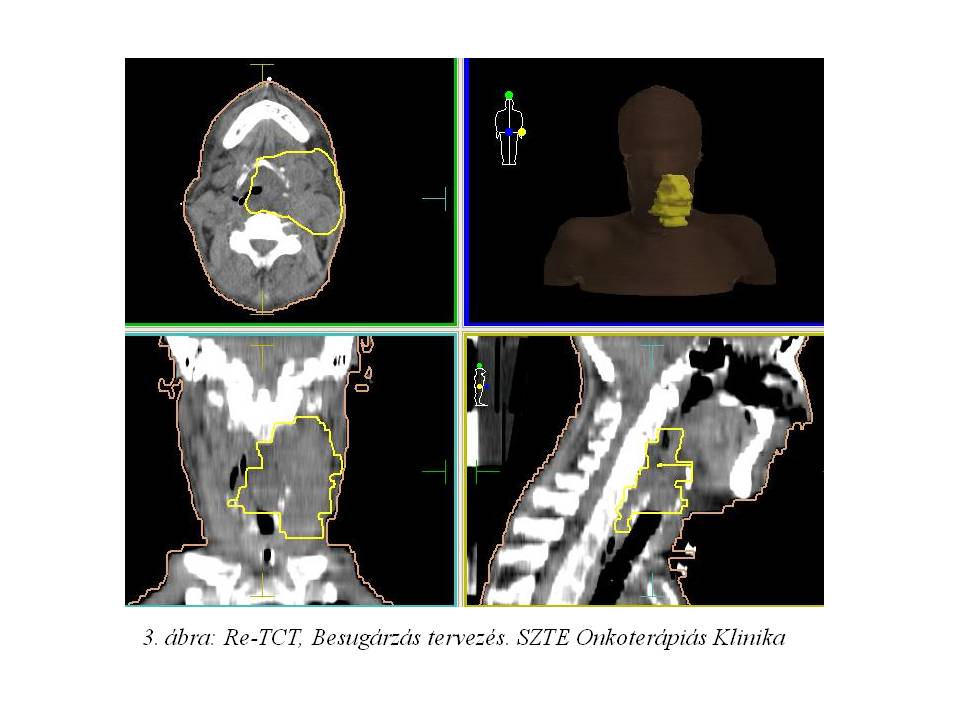

Fizikális vizsgálattal kiváló tumor regressziót észleltünk, ezért re-topometriás CT vizsgálatot is végeztünk (3. ábra: re-topoCT: Besugárzás tervezés, dózis-volumen hisztogramm), mely ugyancsak nagyfokú tumor regressziót véleményezett (a GTV 942 cm3-ről 236 cm3-re csökkent).